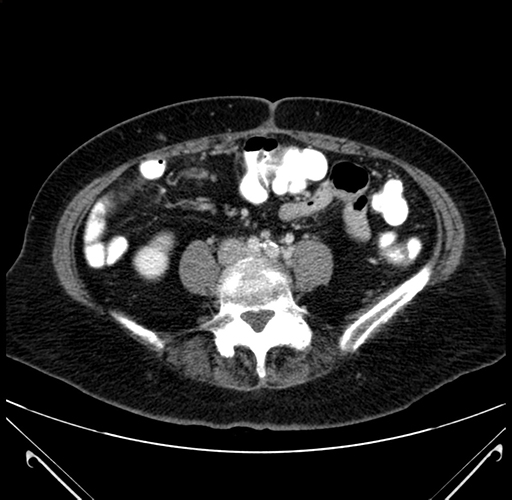

Axial Venous

Coronal Venous